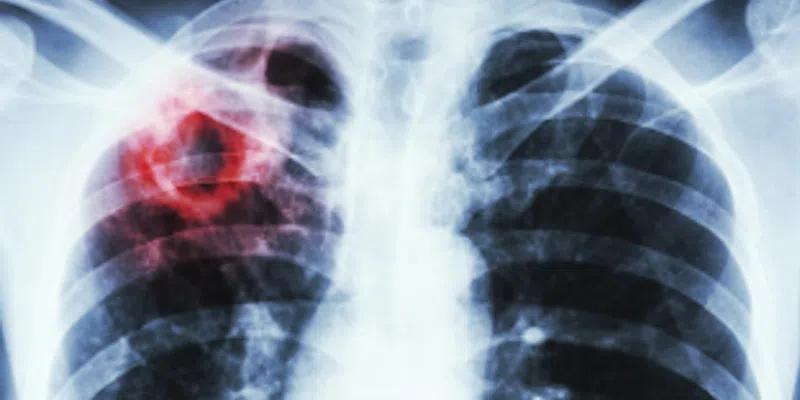

There is an outbreak of tuberculosis, also known as TB, in Nunatsiavut.

According to NL Health Services, TB is a bacterial disease that usually affects the lungs.

It is spread through the air when an infected person coughs, talks, laughs or sings, typically after prolonged exposure to another person who is sick.

Symptoms include a persistent cough, fever, night sweats, and weight loss.